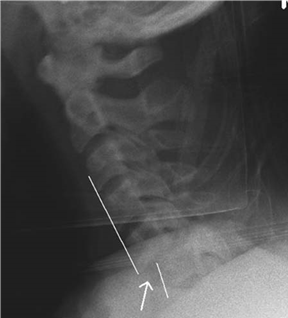

What are your comments about this radiograph?

T he C5 vertebra is displaced by 50% compared with C6, indicating a bifacet dislocation. This radiograph only shows down to C7 and is therefore inadequate for a trauma C Spine lateral radiograph.

How would you manage him now?